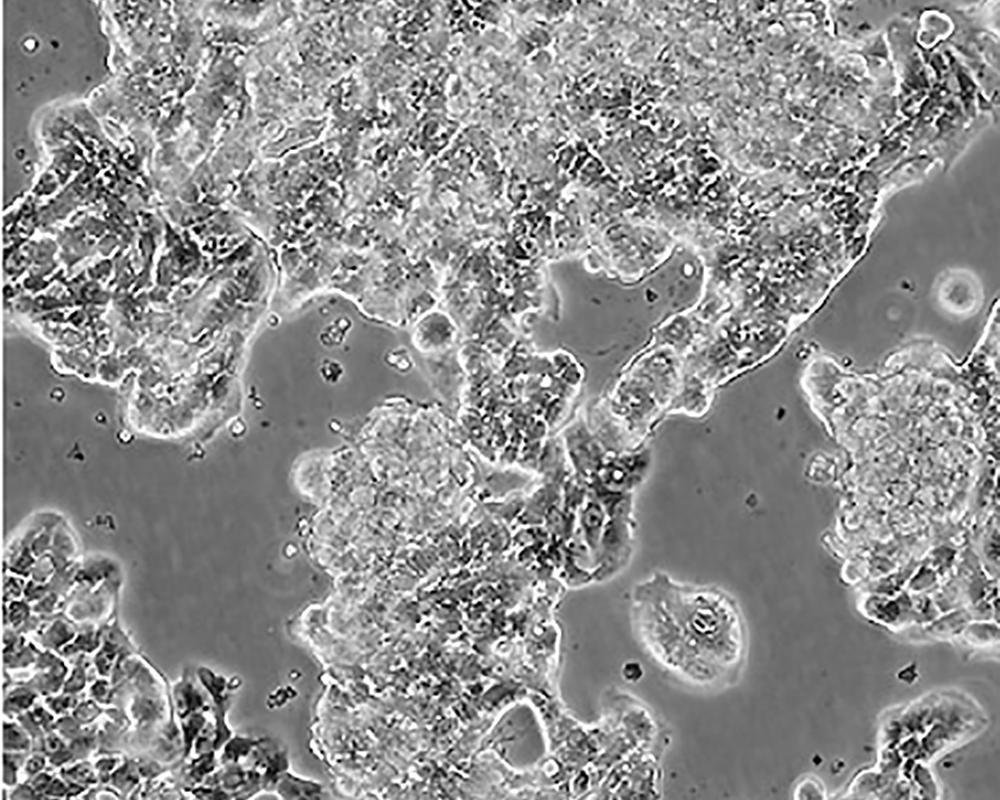

生長特性 adherent

形態特征 epithelial

細胞描述 該細胞產生高水平的黏液素MUC-1 mRNA,低水平的MUC-2 mRNA,但不表達MUC-3基因;表達雌激素受體。